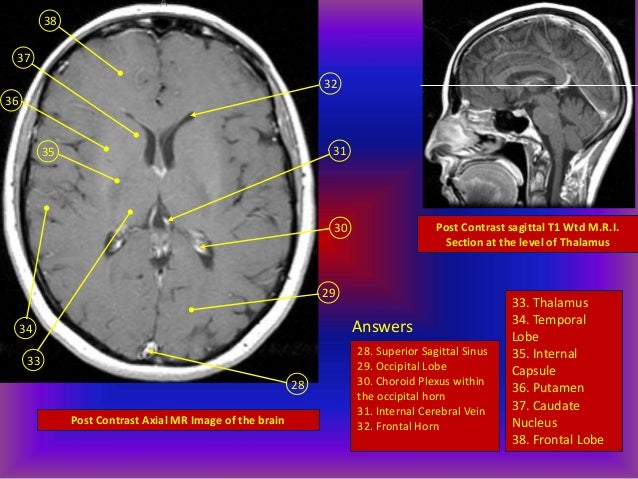

Brain ct scan, anatomy, cerebrum, cerebellum, brain stem, basal ganglia, insula, dr. Learn how this test works, as well as its benefits and risks. It contains information about the normal anatomy and the different types of brain hemorrhage.